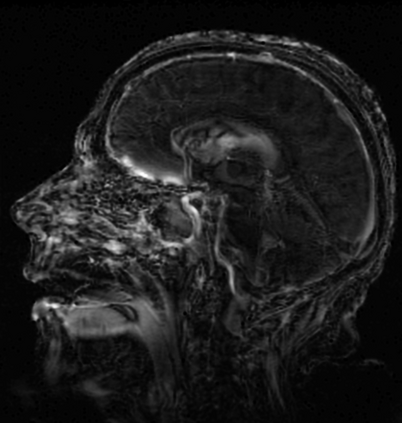

In this study, we aim to initiate the development of Radiology Foundation Model, termed as RadFM.We consider the construction of foundational models from the perspectives of data, model design, and evaluation thoroughly. Our contribution can be concluded as follows: (i), we construct a large-scale Medical Multi-modal Dataset, MedMD, consisting of 16M 2D and 3D medical scans. To the best of our knowledge, this is the first multi-modal dataset containing 3D medical scans. (ii), We propose an architecture that enables visually conditioned generative pre-training, allowing for the integration of text input interleaved with 2D or 3D medical scans to generate response for diverse radiologic tasks. The model was initially pre-trained on MedMD and subsequently domain-specific fine-tuned on RadMD, a radiologic cleaned version of MedMD, containing 3M radiologic visual-language pairs. (iii), we propose a new evaluation benchmark that comprises five tasks, aiming to comprehensively assess the capability of foundation models in handling practical clinical problems. Our experimental results confirm that RadFM significantly outperforms existing multi-modal foundation models. The codes, data, and model checkpoint will all be made publicly available to promote further research and development in the field.